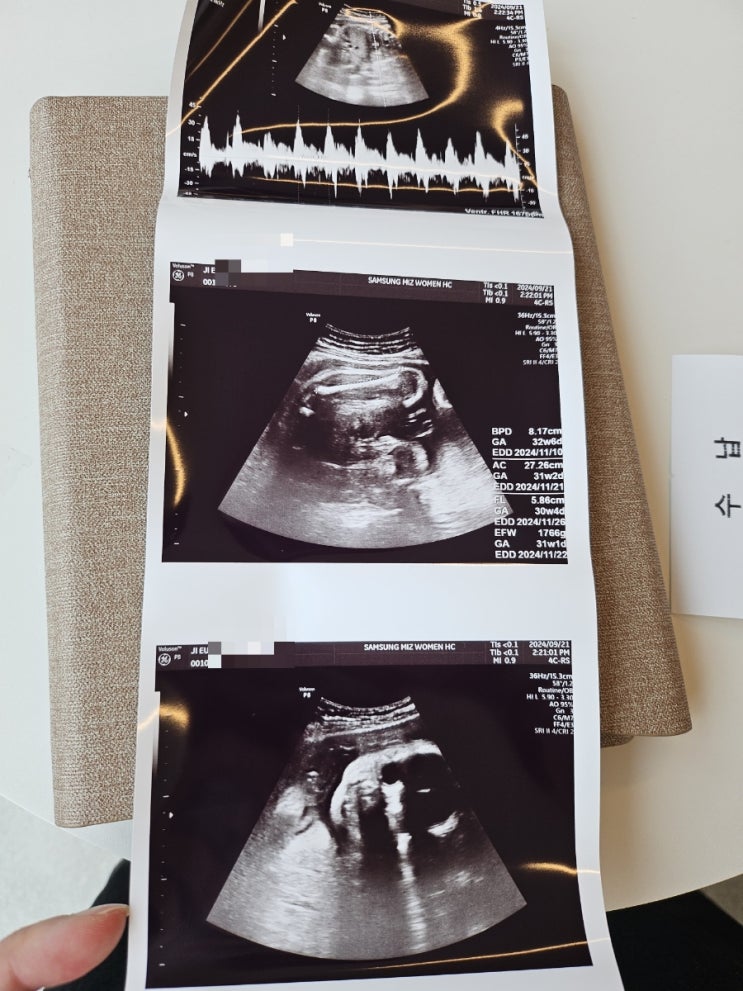

[임신 32주차] 32주차 정기검진, 백일해주사, 제왕절개 날짜 확정

30주에 정기검진을 갔다온 후 다음 진료는 2주 후인 32주에 정기검진 (춈파)를 보러 또 와야한다고 했음 추...